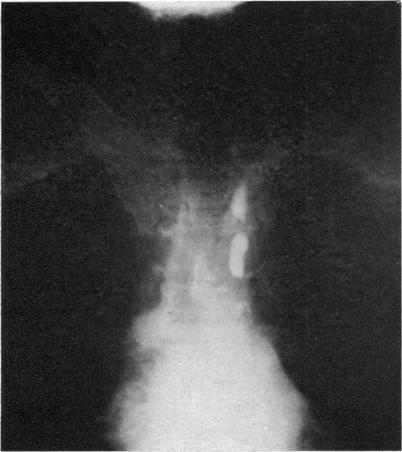

The changes in the thoracic duct were studied in schistosomatic hepatic fibrosis, particularly in cases with ascites. The postmortem findings, lymphangiography, and clinical thoracic duct cannulation showed that, particularly in cases with ascites, the thoracic duct is dilated, pressure within is raised, and the lymph flow is increased. The significance of these findings is discussed in relation to the site and the treatment of ascites.